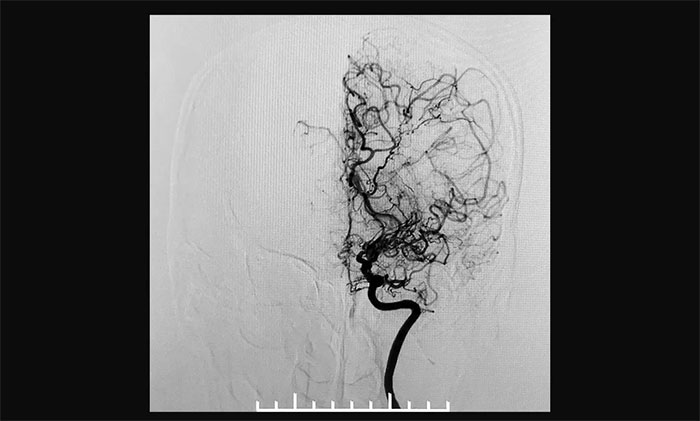

上海藍(lán)十字腦科醫(yī)院神經(jīng)外科6A病區(qū)專家宮衛(wèi)東主任介紹,煙霧病又稱“自發(fā)性腦底動(dòng)脈環(huán)閉塞癥”,是一組以雙側(cè)頸內(nèi)動(dòng)脈末端和(或)大腦前動(dòng)脈、大腦中動(dòng)脈起始部緩慢進(jìn)展性狹窄以致閉塞后,腦底出現(xiàn)代償性異常血管網(wǎng)為特點(diǎn)的腦血管病,因其血管造影形似“煙霧”,故稱為“煙霧病”。

▲異常血管網(wǎng)在腦血管造影時(shí)形似“煙霧”

據(jù)文獻(xiàn)記載,煙霧病于20世紀(jì)60年代在日本被首先發(fā)現(xiàn),其后世界其它國(guó)家相繼發(fā)現(xiàn)相關(guān)病例。1969年,日本學(xué)者Suzuki及Takaku將該病稱之為“moyamoya”。“ moyamoya”在日語(yǔ)中意為“噴出的煙霧”,“煙霧病”由此得名。